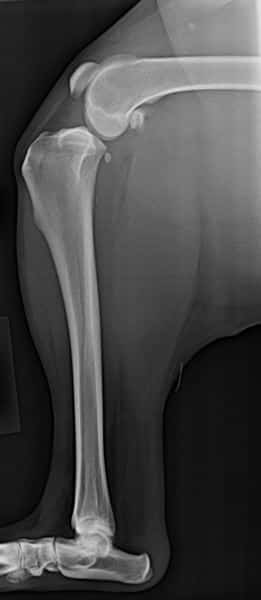

Before TPLO